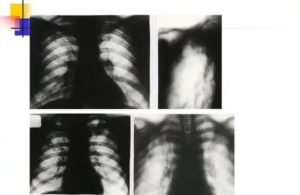

- Дыхательная система — легкие и бронхи. Заболевание и его лечение способны вызвать ателектаз – спадание одной или нескольких долей легкого. Вследствие чего происходит дисфункция органа. Процесс ателектаза сопровождается болевыми ощущениями в очаге поражения, нарушением сердечного ритма и «прыжками» давления из-за неспособности легких работать в полном объеме. В этом случае своевременное лечение и реабилитация после туберкулеза позволяют продлить и повысить качество жизни конкретного человека. Кроме ателектаза осложнением после излечения туберкулеза становится спонтанный, закрытый пневмоторакс – скопление газов в плевральной полости, которое становится причиной избыточного давления на ткани легких. Сопровождается острой болью, затрудненнием дыхания. Без профессиональной помощи вызывает коллапс легкого.

Фото 4. В первую очередь возбудители туберкулезного заболевания попадают именно в дыхательную систему человека.